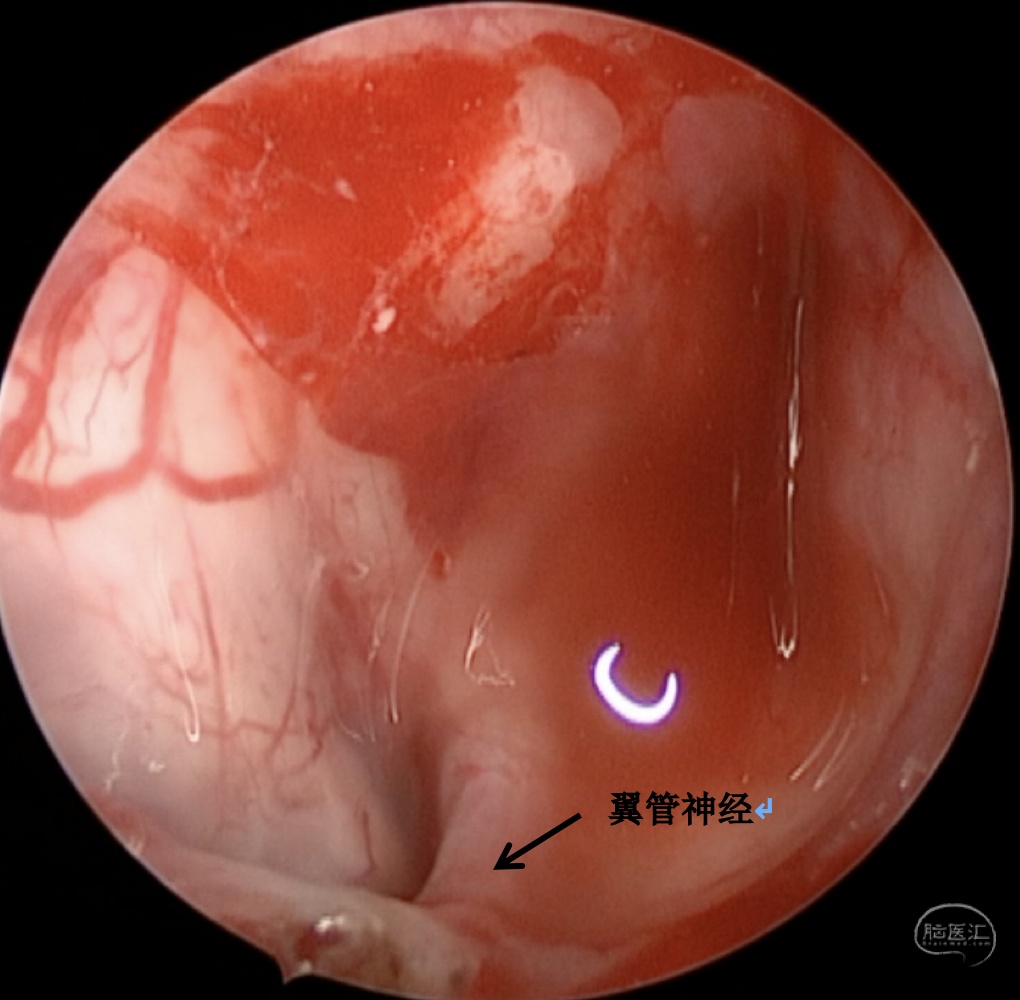

手术方案:内镜经鼻经翼突入路

术中情况: